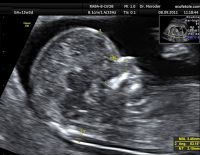

Độ mờ da gáy 1.5 khi thai 12 tuần có bình thường không?

Độ mờ da gáy 1.5 có phải là chỉ số bình thường không khi thai được 12 tuần tuổi. Đây là bước siêu âm thai quan trọng trong 3 tháng đầu mà mẹ bầu cần thực hiện để chẩn đoán các dị tật bẩm sinh...